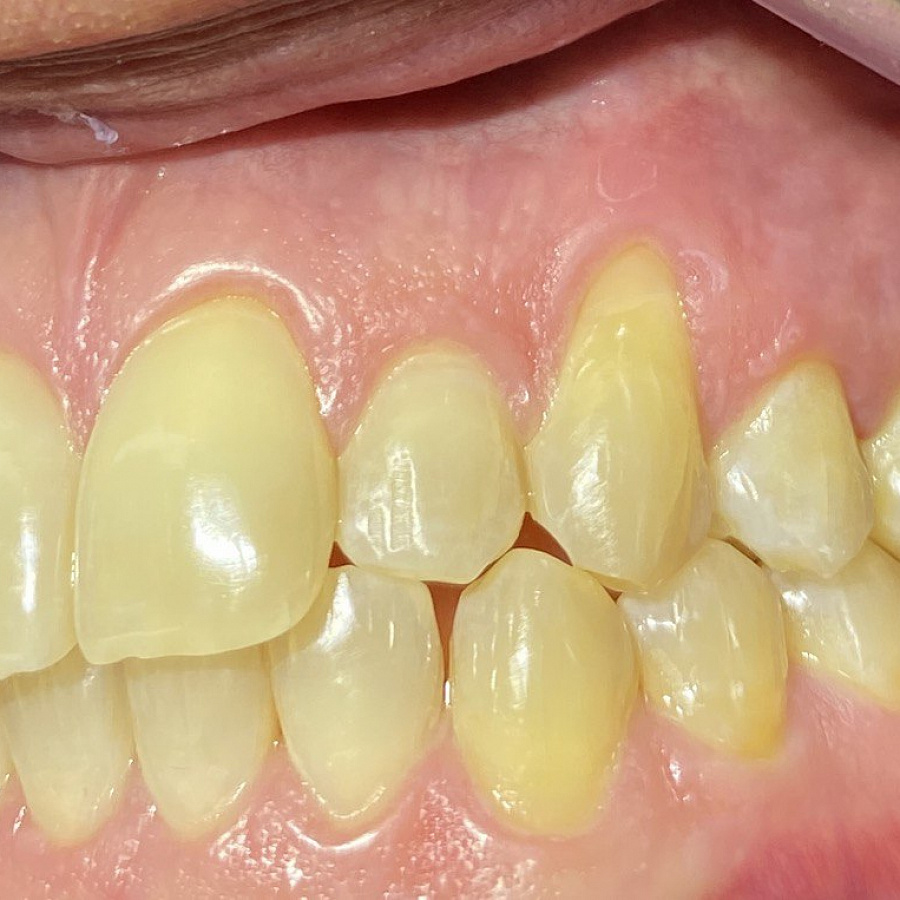

Пациент обратился с жалобами на неровные передние зубы верхней и нижней челюстей.

сужение зубных рядов,

обратное перекрытие в области фронтальных зубов слева,

разворот по оси передних зубов верхней и нижней челюстей,

стираемость эмали зубов,

индивидуальную микродентию 12 и 22 зубов.

Ортодонтическое лечение с помощью элайнеров длилось 10 месяцев. Далее последовало протезирование и установка виниров.

Результат лечения